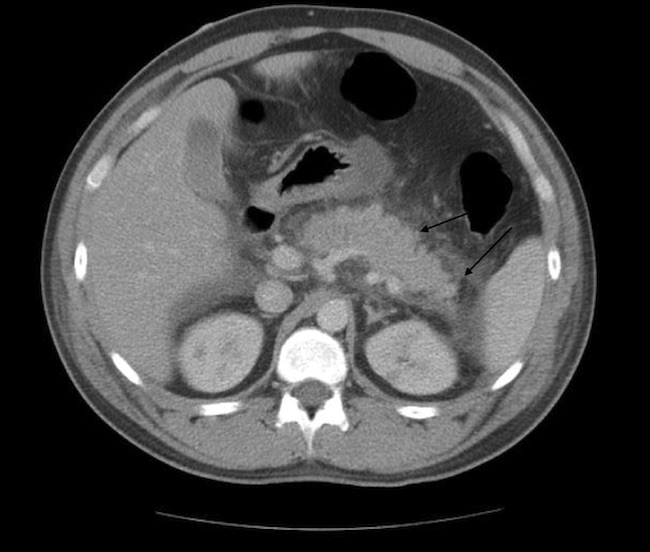

The patient’s symptoms worsened over the course of admission. The lipase level continued to rise and reached 5156 U/L on day 2 of admission. Findings of a follow-up CT scan of the abdomen (Figure 2) and magnetic resonance cholangiopancreatography (MRCP) (Figure 3) were consistent with severe pancreatitis.

Figure 2. CT scan of the abdomen on day 3 showing moderate to severe peripancreatic inflammatory changes, mainly affecting body and tail of pancreas (arrows).